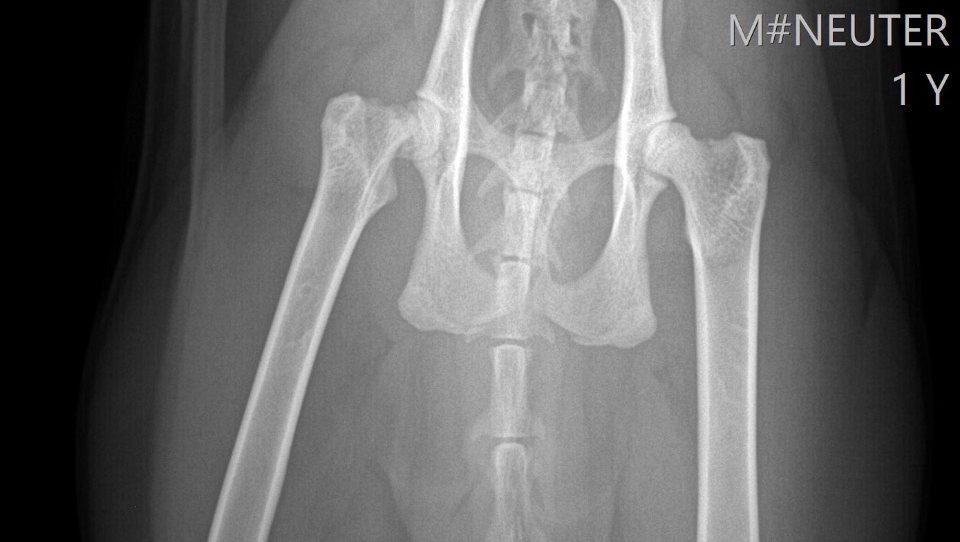

Xrays ⬇️

We rushed him to the vet the next day. That alone cost nearly $700, which completely drained us. They did X-rays and gave him pain meds, and the next day we got the news: Puddles has a fractured femur near the hip, and he needs a surgery called an FHO (femoral head ostectomy) to be able to walk normally again without pain.